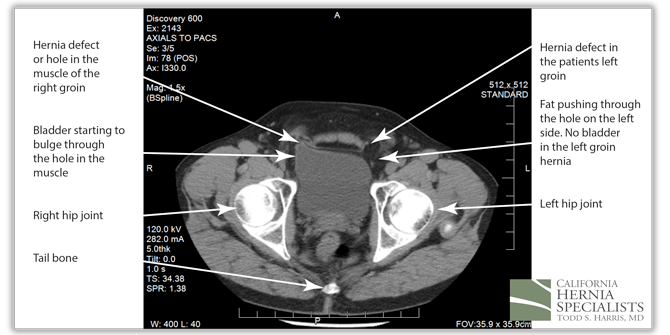

He was seen by his primary care physician in Arizona who ordered a CAT scan. The scan showed the images below including a large portion of his bladder in the right hernia. He also had a moderate sized fat containing hernia in the left groin.

The CAT scan image above shows normal muscles of the abdominal wall with no evidence of a hole, or a hernia.

However, in this CAT scan image, there is a noticeable hole in the lower muscle wall, and the start of an inguinal hernia both on the left and the right side of the groin.

The bladder can be seen squeezing through the hole in the muscles within the patients right groin (left side of the CAT scan image). On the patients left side (right side of the image), there is only fat pushing through the hernia defect.